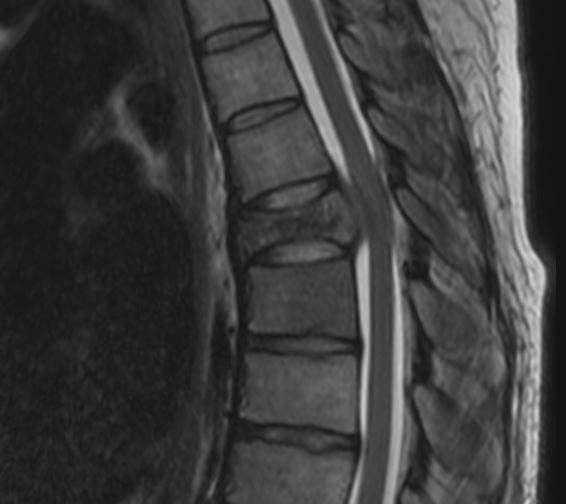

Sinterungsfraktur BWS MRT

Darstellung einer Sinterungsfraktur im 6. Brustwirbelkörper in einer sagittalen T2 Bildgebung.